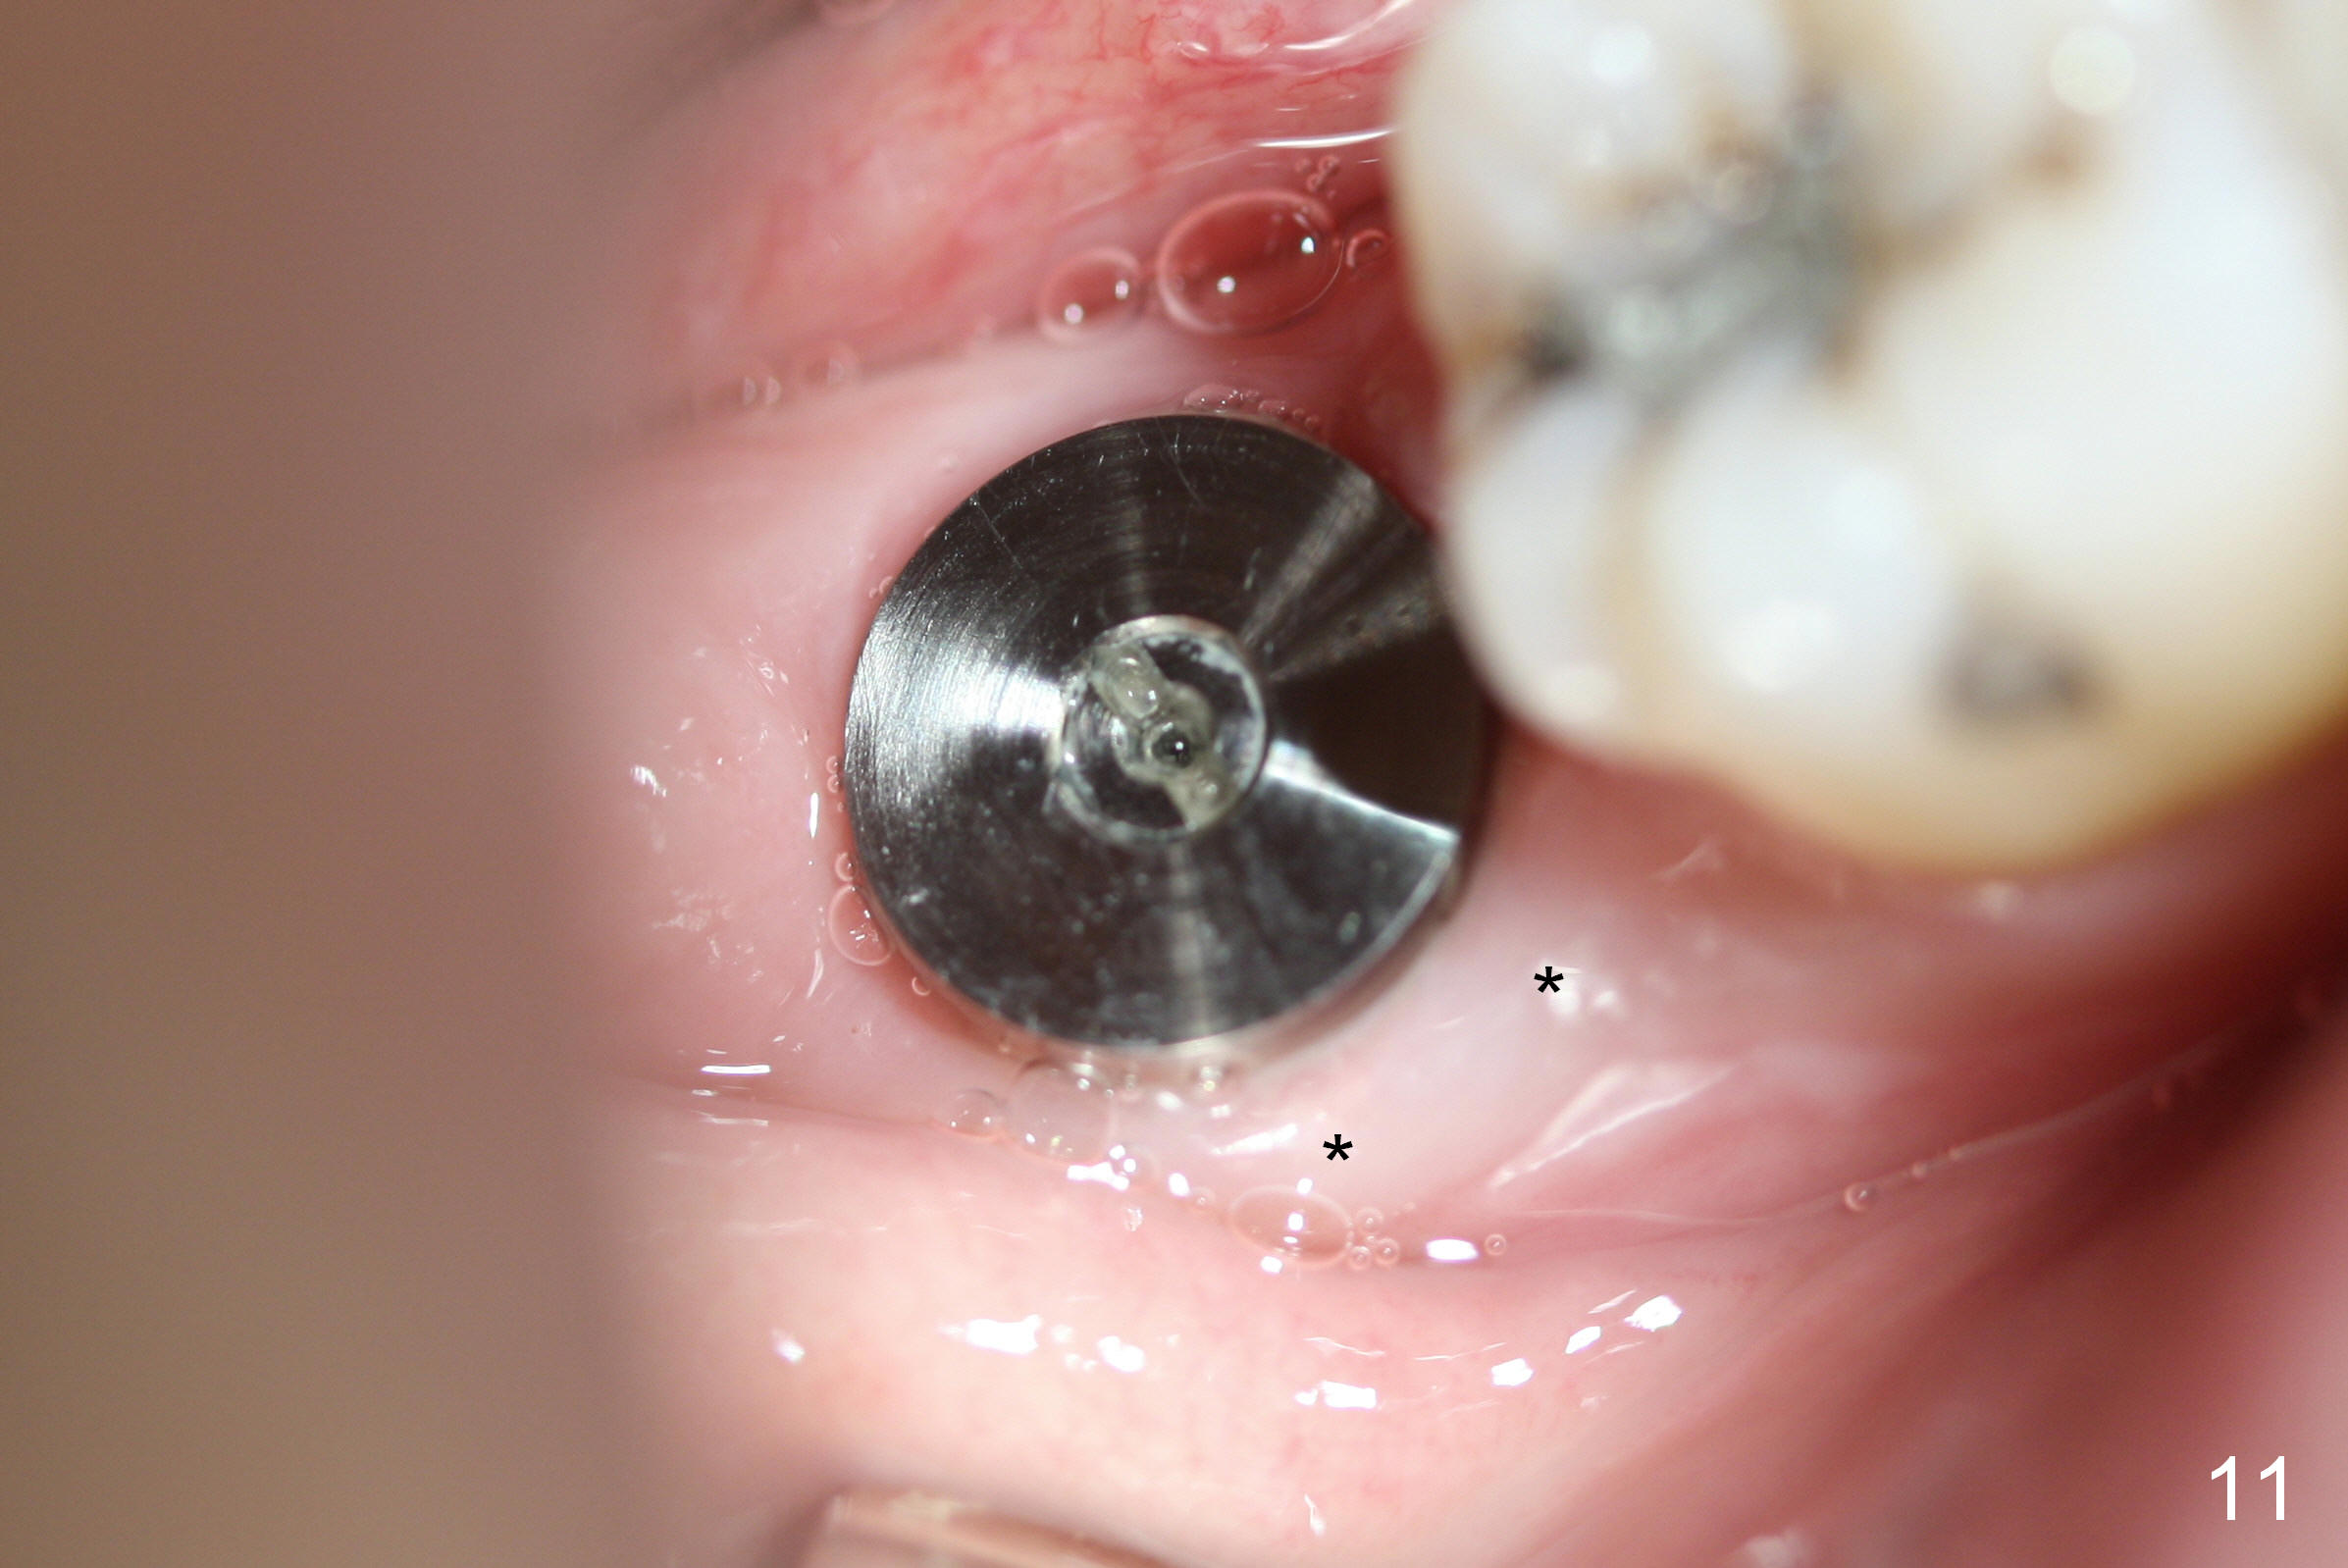

The tooth #31 of a 38-year-old lady has endo perio disease (Fig.1). Due to the large periapical lesion, there will be no solid (new) bone available for primary stability of an immediate implant (Fig.2: 7x17 mm). Yellow dashed line represents the upper border of the Inferior Alveolar Canal (IAC). Infiltration anesthesia is administered first. The mesiodistal widths of the root of the extracted tooth are 10 and 7 mm at the coronal and apical ends, respectively; the buccolingual ones 7 and 5 mm; the length 17 mm (Fig.3). The socket appears much larger than the root (Fig.4). To prevent paresthesia, no drills are used. Instead, a series of tap drills (6,7,8x17 mm) are sequentially inserted into the socket. The largest tap (Fig.5 T; 8x17 mm) binds to the socket securely with separation from IAC. Block anesthesia has to be administered before removal of the tap. A tapered implant (8x17 mm) is placed with insertion torque greater than 60 Ncm (Fig.6 I); allograft mixed with Osteogen is placed around the implant (*). Collagen dressing covers the opening of the remaining socket. The wound is protected with perio dressing, which is partially secured by an abutment (A in Fig.6). No paresthesia is reported by the patient a few hours postop.